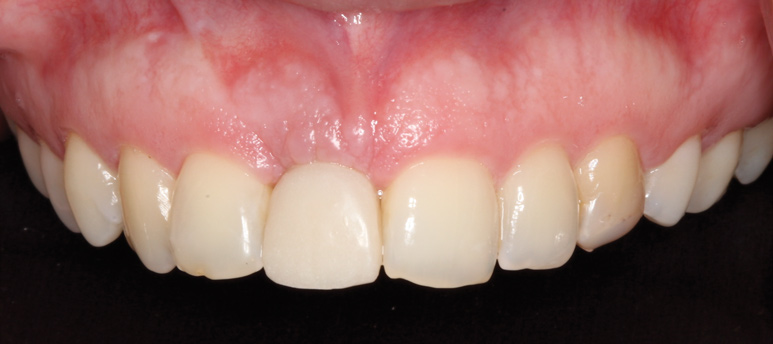

A 33-year-old woman presented with a buccal fistula at the apex of No. 8, and there was an 8-mm mid-buccal probing depth (Figure 1). The tooth had been treated multiple times by an endodontist. Based on the tooth's dental history, mobility, and its poor endodontic and periodontal prognosis, it was deemed hopeless and scheduled for extraction (Figure 2).

Fig 1. Fistulous tract at apex of tooth No. 8 (arrow).

Figure 1

Fig 11. Frontal view 4 months postoperatively.

Figure 11

Fig 19. Final screw-retained crown on implant at site No. 8.

Figure 19